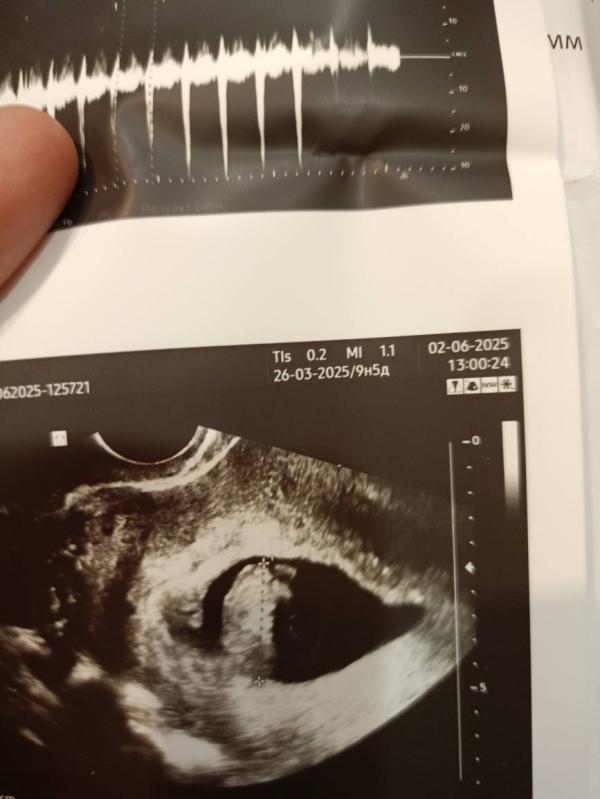

В понедельник 2ого июня я была на УЗИ и на приеме.

Начну пожалуй с УЗИ ( это было мое второе УЗИ, первое было на сроке 4-5 недель , тогда я только узнала о тебе и на следующий же день поехала на первое УЗИ 😅

Врач всё смотрит смотрит, я только начинаю нервничать как она включает мне послушать твое сердечко малыш❤

По узи всё хорошо, срок беременности 9.1 день по малышу🤰Ручки и ножки только образовываются, скоро он будет полноценным человечком😍( Расти малыш!). Малыш прекреплен по задней стенке , я уверена, что он мальчик , сынок!

На фото второе и первое узи❤🔥